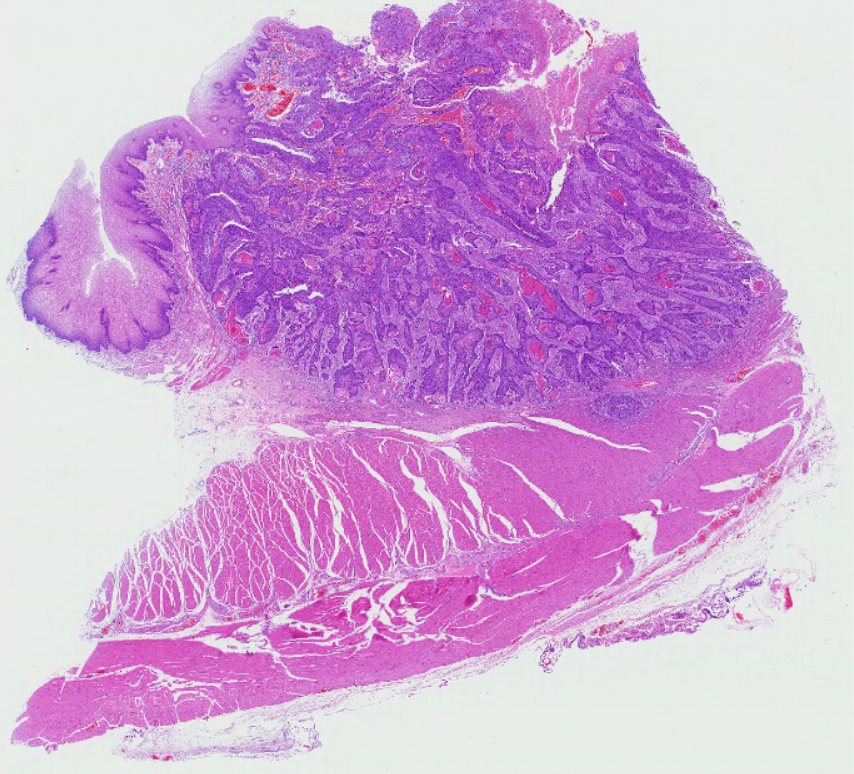

5 胃溃疡

1.全景图